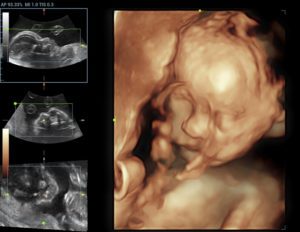

Стоимость на ультразвуковую диагностику также варьируется. Обычное исследование с получением черно-белого плоского изображения – самый демократичный вариант. При трехмерном УЗИ картинка высокого качества, цветная и объемная. Можно разглядеть даже малейшие черты малыша.

4D-исследование позволяет получить видеозапись, поскольку четвертым измерением выступает время. Последние два вида пренатальной диагностики в основном встречаются в частных клиниках, цена на них достаточно высока.